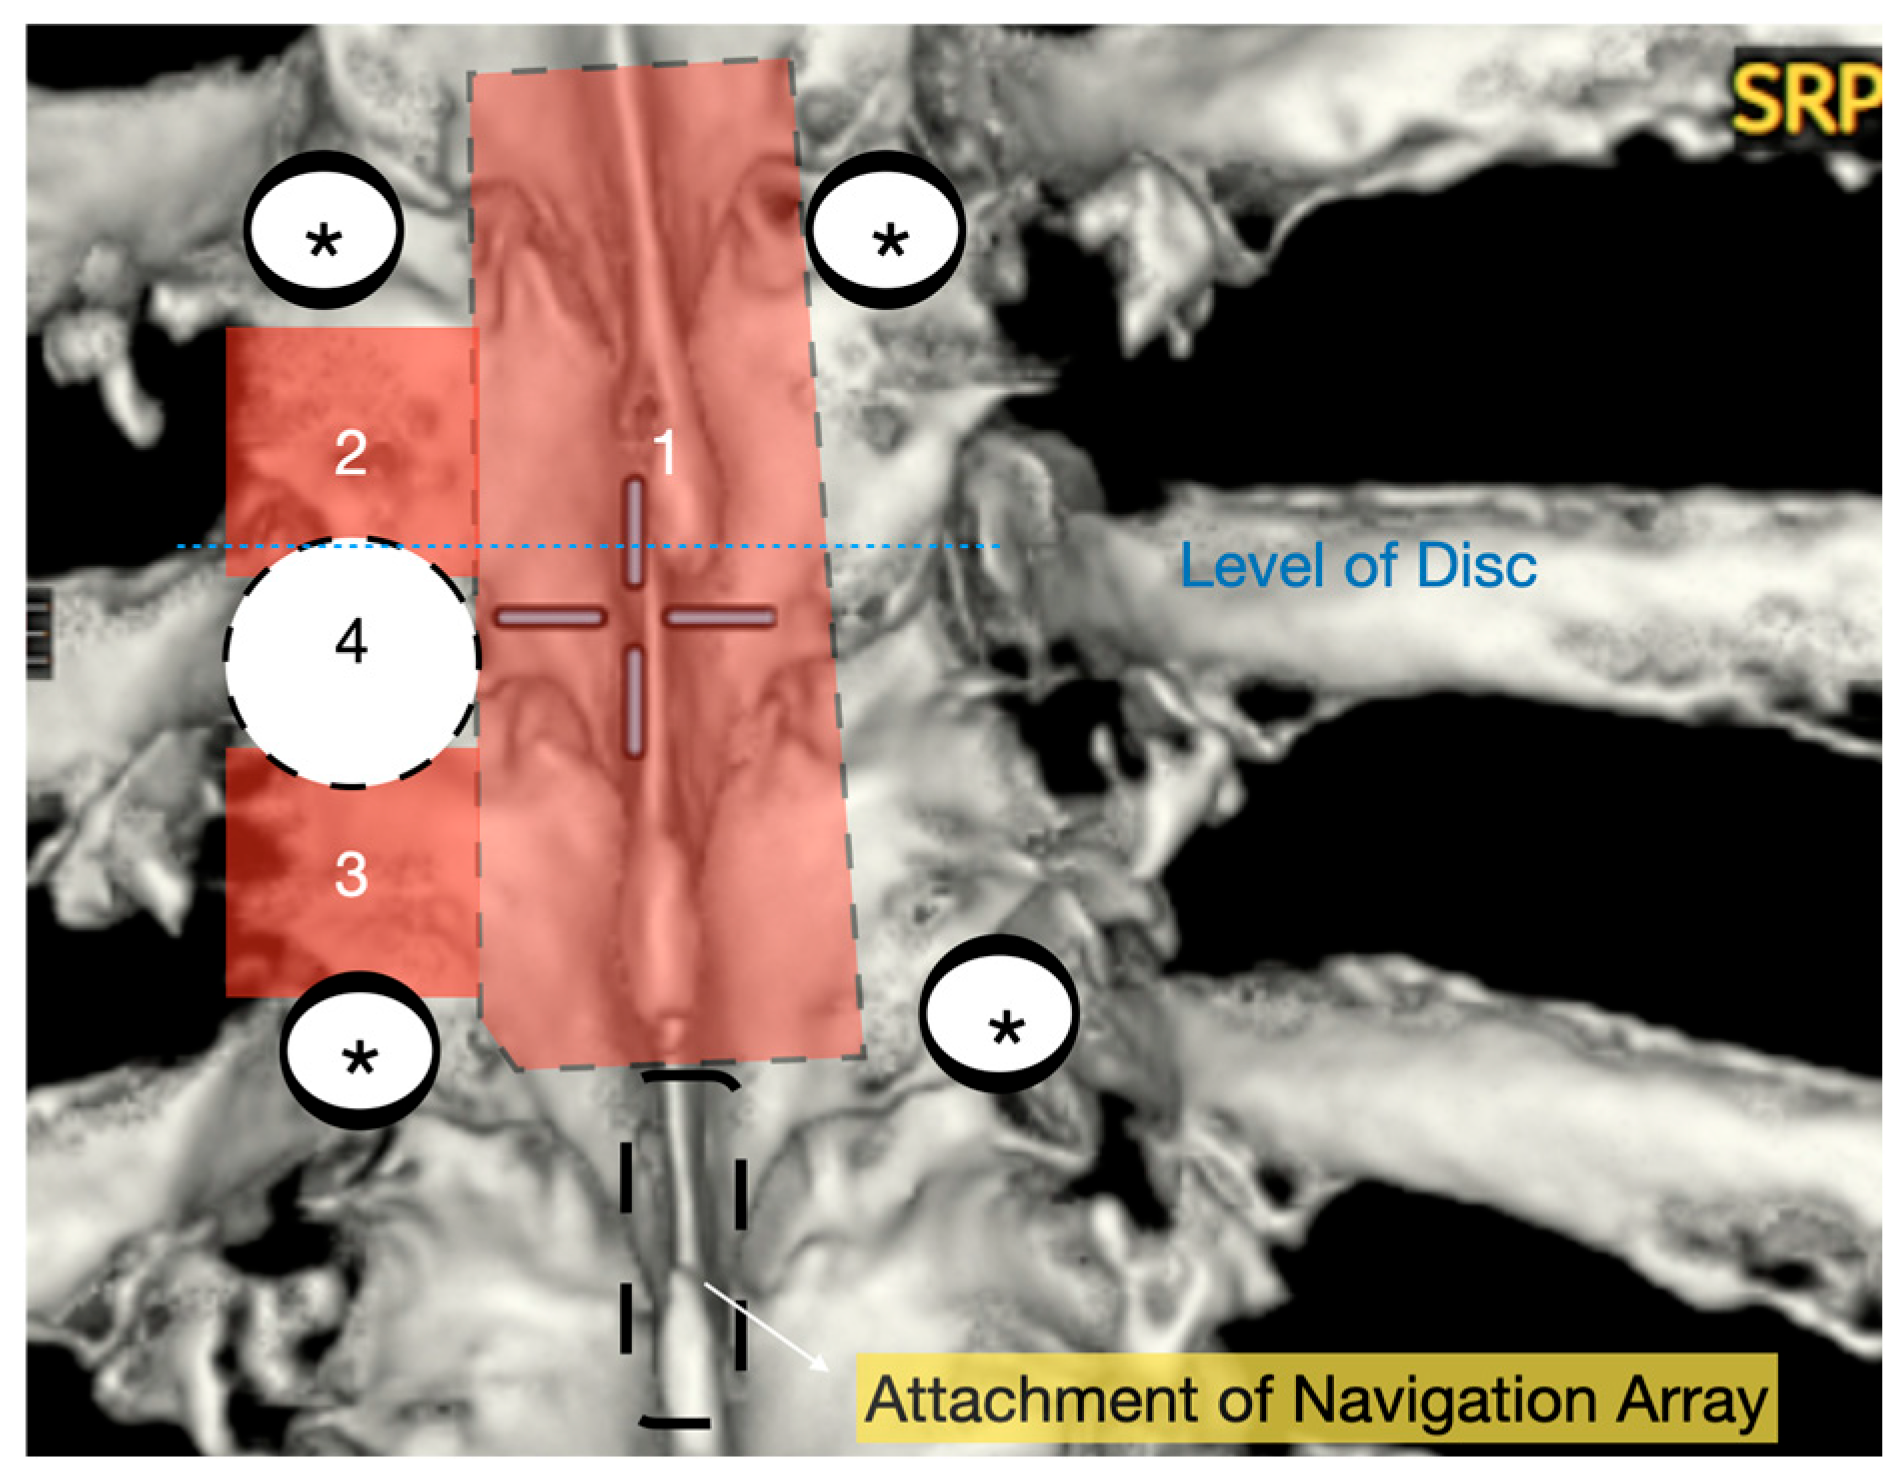

Patients were positioned prone on an Allen Table with chest bolsters and head stabilization using a Mayfield clamp. Intraoperative neuromonitoring (MEPs and SSEPs) and neuronavigation (O-Arm with StealthStation) were employed in all cases. A midline incision was made according to the preoperative rib counting and extended caudally by one level below the lowest planned instrumentation to allow for secure placement of the navigation reference array (Figure 1). An initial O-Arm spin was acquired, and pedicle screws were placed one level above and two levels below the herniated disc. The pedicles immediately inferior to the disc space were deliberately left uninstrumented to facilitate ipsilateral pediculectomy and optimize access to the ventral spinal canal.

A wide en bloc laminectomy was performed at the disc level and one level above and below using a Misonix bone scalpel. This was followed by ipsilateral superior and inferior facetectomies and complete pediculectomy to establish an oblique and spacious working corridor toward the ventral spinal canal (Figure 1). Under the operating microscope, the dura was opened in the midline with a no. 15 blade, and the arachnoid was incised sharply. CSF was allowed to drain passively for 10–15 min to reduce intradural pressure and promote relaxation of the spinal cord. The table was then tilted approximately 6–10 degrees to the contralateral side to allow for gravity-assisted displacement of the cord away from the operative field (Figure 2a,b and Figure 3).

Figure 1. Three-dimensional reconstruction of area of interest (T9–11) with representation of osteotomies carried out with bone scalpel. 1: En block laminectomy; 2: ipsilateral upper facetectomy; 3: ipsilateral lower facetectomy; 4: ipsilateral pediculectomy. *: screws.